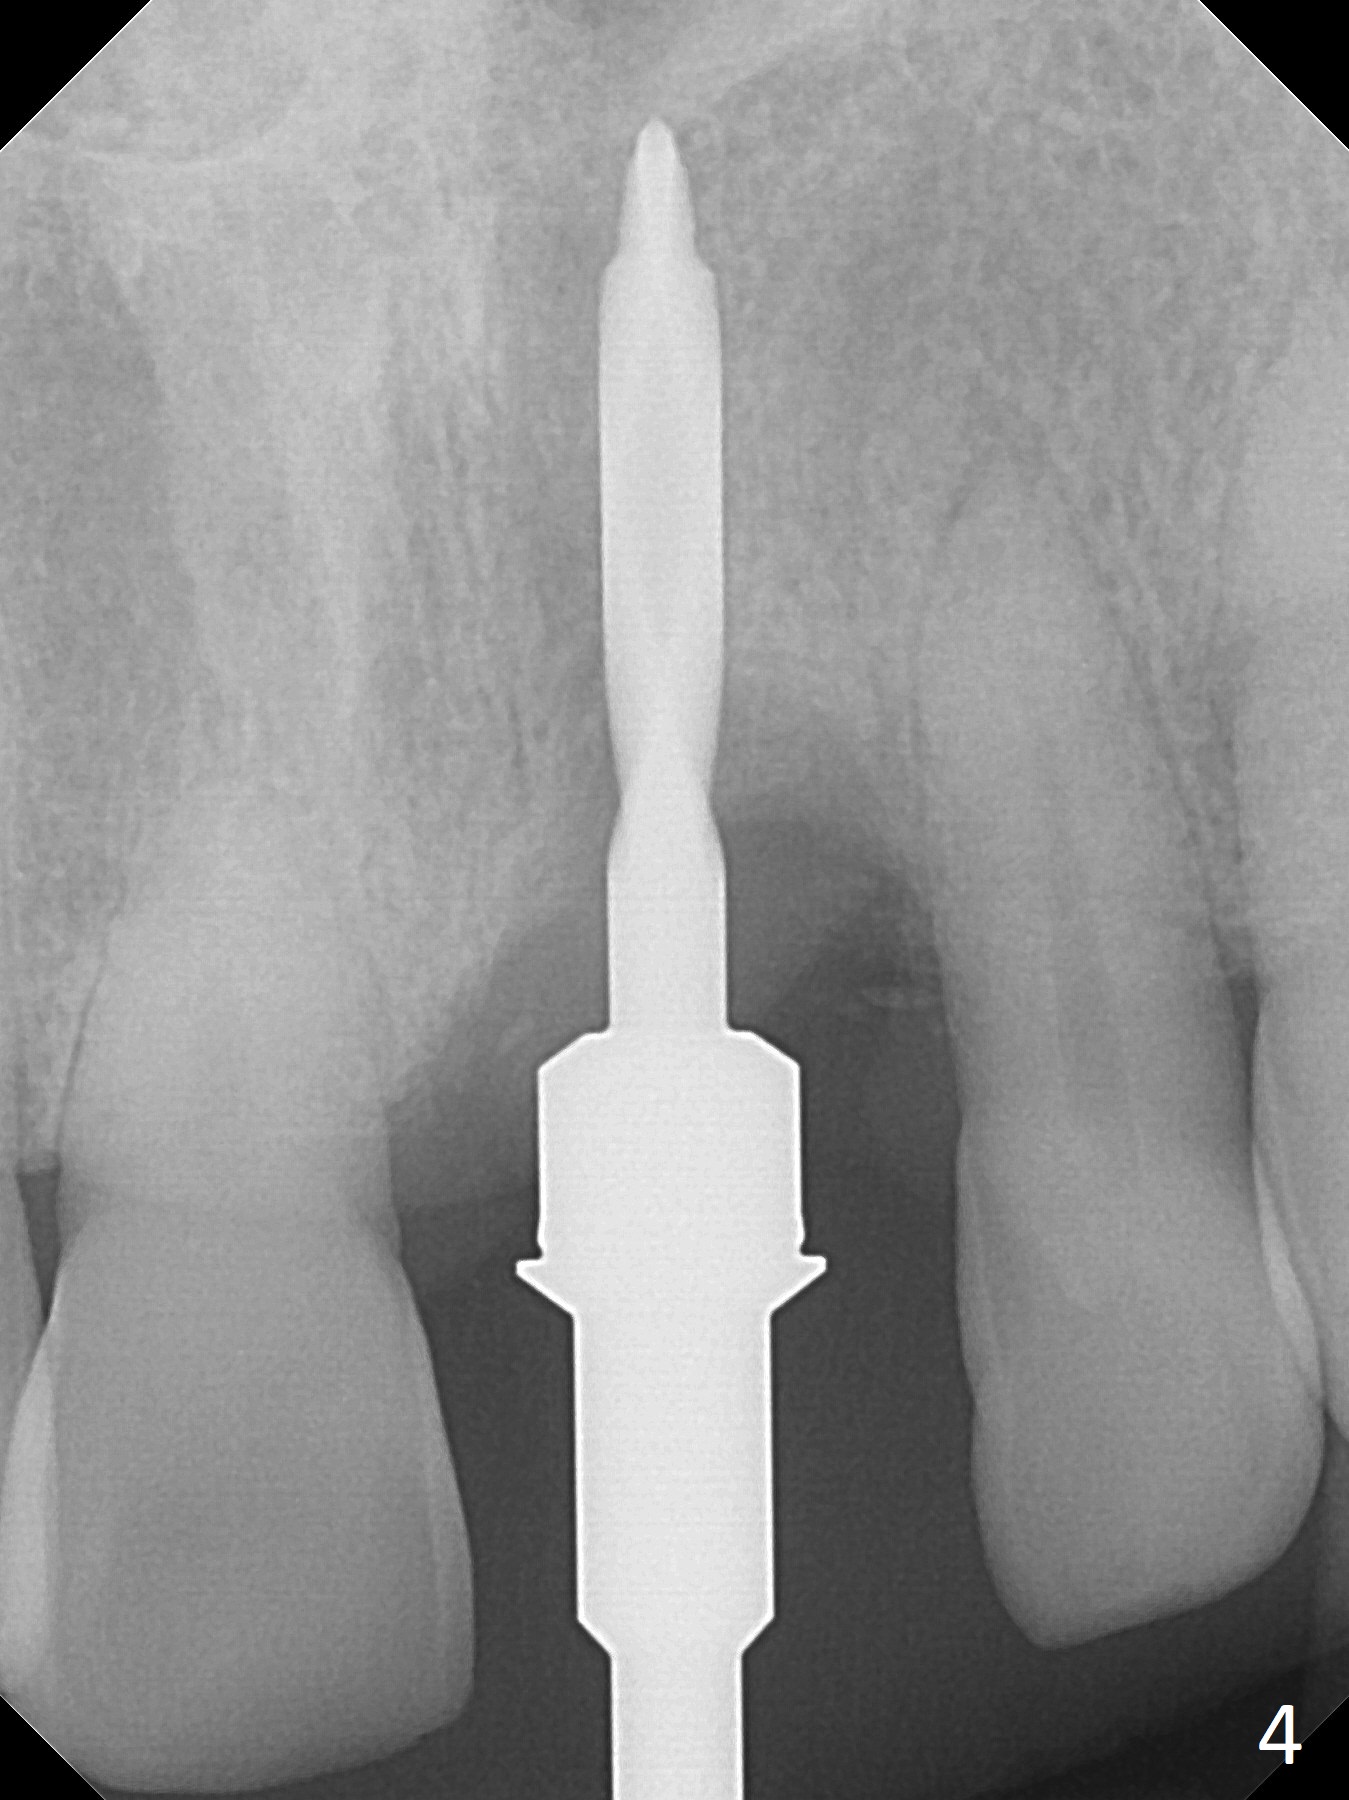

Preop examination shows mobility I of the teeth #8 and 10 and apparent occlusal trauma from #22-26 implant bridge. After occlusal equilibrium, incision reveals low, but moderate ridge at #9 (Fig.1). Fig.2a is a cross section of a normal upper incisor socket with thin buccal plate (B) and thick palatal one (P). It is difficult to initiate osteotomy in the oblique palatal wall when the buccal plate is resorbed (Fig.2b). In this case with horizontal buccal and palatal plate bone loss, the socket bottom is flat (Fig.2c), easy for osteotomy (Fig.2d green arrow, Fig.3). The initial osteotomy deviates mesial (Fig.3). To avoid perforation into the Incisive Canal, the trajectory is changed (Fig.4). After use of the final drill (3 mm), the coronal Incisive Canal is perforated. Following placement of a 3.5x13 mm implant and 4.5x5.5(4) mm abutment, Vanilla Graft is placed (Fig.5 *) to repair the perforation. Retrospectively, the coronal end of the Incisive Canal is revealed at incision (Fig.1 *). The initial osteotomy should be slightly more distal (Fig.3 black line). The buccal plate looks bulky due to placement of the abutment and bone graft 1 week postop (Fig.6,7 (crown dislodgement)). The bone graft appears to remain in place 2 months postop (Fig.8). Impression is taken because of instability of the immediate provisional (Fig.9 after Laser gingivectomy). The gingiva and buccal plate remain healthy 4.5 months postop (Fig.10). A permanent crown is cemented (Fig.11).